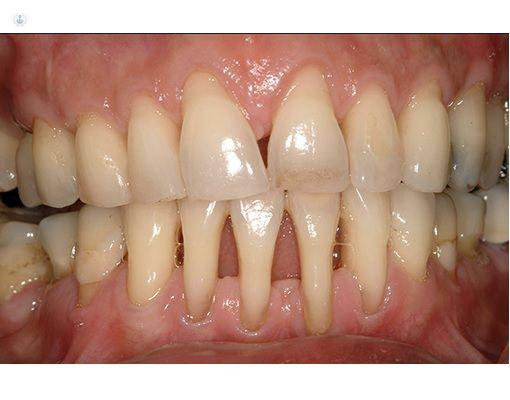

Es una infección grave de las encía que daña el tejido blando alrededor de los dientes. es una infección grave de las encías que daña el tejido blando alrededor de los dientes. Si no se trata, puede destruir el hueso en el que se apoyan los dientes, lo que puede causar que los dientes se aflojen o incluso se produzcan pérdidas dentales

Si no tiene una buena higiene la placa y el sarro se acumulan en la base del diente, esto hace que la encia se inflame y esta misma se distancie de la superficie dentaria dando paso a una bolsa periodontal. Estas se llenan de bacterias provocando infecciones, si estas continuan con el tiempo, al final destruyen los tejidos y el hueso al rededor del mismo, asi perdemos estabilidad y sustencion de nuestro diente.

Sintomas

Mal aliento constante

Encias rojas o inflamadas

Dolor, sangrado en las encias

Dolor al masticas

Dientes flojos o sencibles